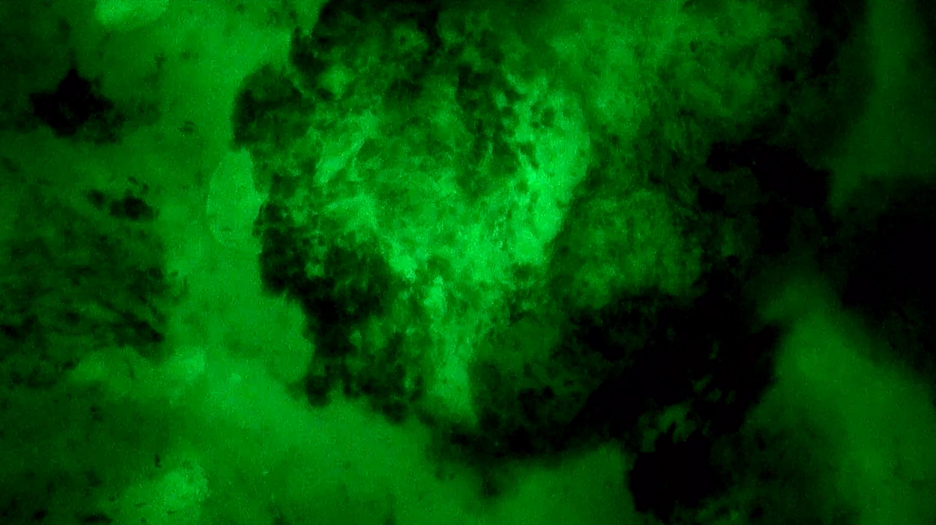

精準(zhǔn)手術(shù)路徑